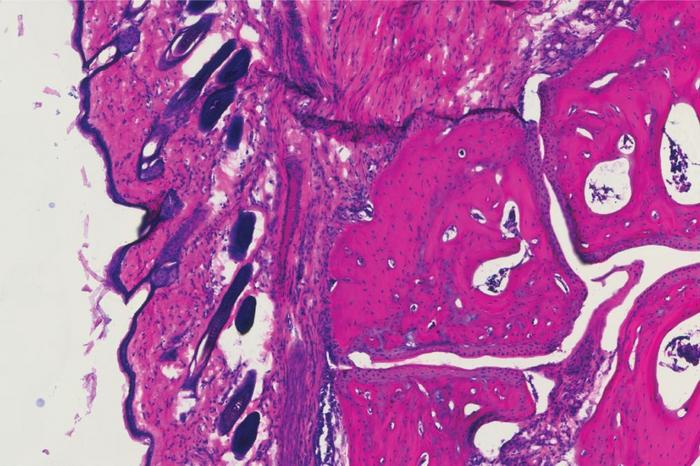

A histology showing the ankle joint of a mouse four days after receiving the new antibody treatment, V11 sFc.

Ravetch lab at The Rockefeller University